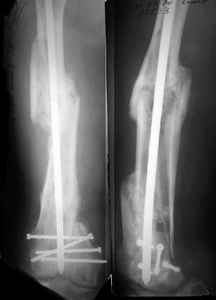

I presented a series of ~25 such cases at EuroTrauma'2004. Many cases were discussed here. I attach am example. Look also recent cases at http://www.hwbf.org/hwb/conf/alex58/scfx.htm,

http://www.hwbf.org/hwb/conf/alex63/alex63.htm

THX, initial images are

1,

2.

At that moment we had in stock only the 10 mm solid nails so of course there was no idea about early weight bearing. But it was quite enough for early knee ROM excersises (see attached). Two locking screws through the distal block provided that.